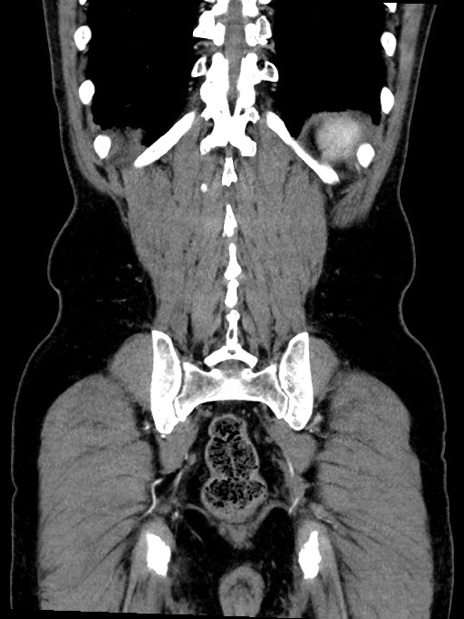

症例35(冠状断像)

【症例】70歳代 男性

【主訴】腹部膨満、嘔吐

【現病歴】昨日より腹部膨満感出現。本日増悪し、仙痛出現。嘔吐あり、受診。

【既往歴】糖尿病、胆摘後

【身体所見】BP 149/80mmHg、HR 74/min、BT 35.9℃、腹部:膨満、軟、圧痛なし。腸雑音減弱あり。上腹部正中切開瘢痕あり。

【データ】WBC 13500、CRP 1.72